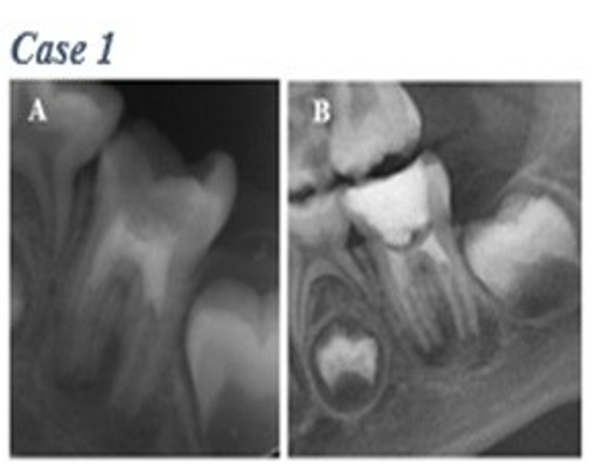

Figure 3. Failure category. Case 1. Mandibular left first molar. Failed case, patient was symptomatic 3 months after completing the treatment. (A) Operative radiography. (B) Follow-up radiograph at 3 months postoperatively

Root development and healing of the periapical tissues may take longer in some cases. In the incomplete healing group, in all cases, the periapical pathology was completely healed; this satisfies at least 1 success criteria of treatment. In these RETs cases with two-year follow-up, complete healing occurred within the first 9 months [14]. In the study of Çehreli et al. [19], similar to this study, the cases were clinically asymptomatic for the first 3 months, showed complete radiographic recovery and an increase in root size was observed at 9 months. In cases where clinical symptoms and signs persist and/or increase in periradicular lesion size considered unsuccessful in RETs, a second RETs entry or apexification procedure should be started to preserve the patient’s natural tooth structure and restore function [8]. In one failure case detected in this study, apexification with MTA was performed.